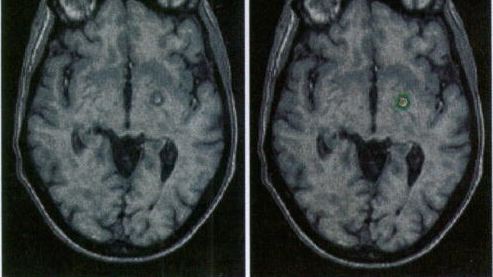

80. Allwood MJ Cobbold AF and Ginsberg J. Peripheral vascular effects of noradrenaline, isopropylnoradrenaline, and dopamine.  Br. Med. Bull., 1963, 19:  132-136.